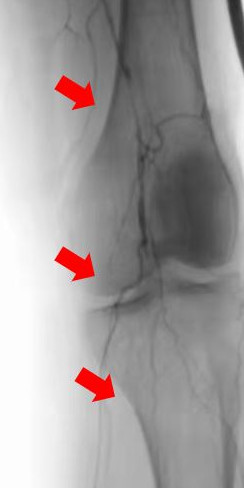

箭頭所示:右腘動(dòng)脈血栓栓塞,血流中斷

箭頭所示:左股、腘動(dòng)脈血栓栓塞,血流中斷